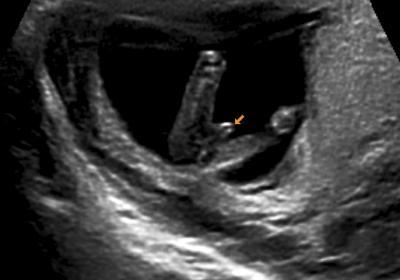

anbei ein us-bild aus 12+4. man guckt von unten auf den popo und sieht quasi die unterschenkel von hinten. der doc hat dankenswerterweise einen pfeil im bild platziert, sodass bauchzwergs geschlecht kein geheimnis mehr ist

@ us-bild: das bild wurde in einer spezialklinik bei der nackenfaltentransparenzmessung gemacht. die geräte dort waren superklasse und der doc hat sich ewig lange zeit genommen. insgesamt wurde fast eine dreiviertelstunde geschallt - gottseidank über den bauch und nicht vaginal